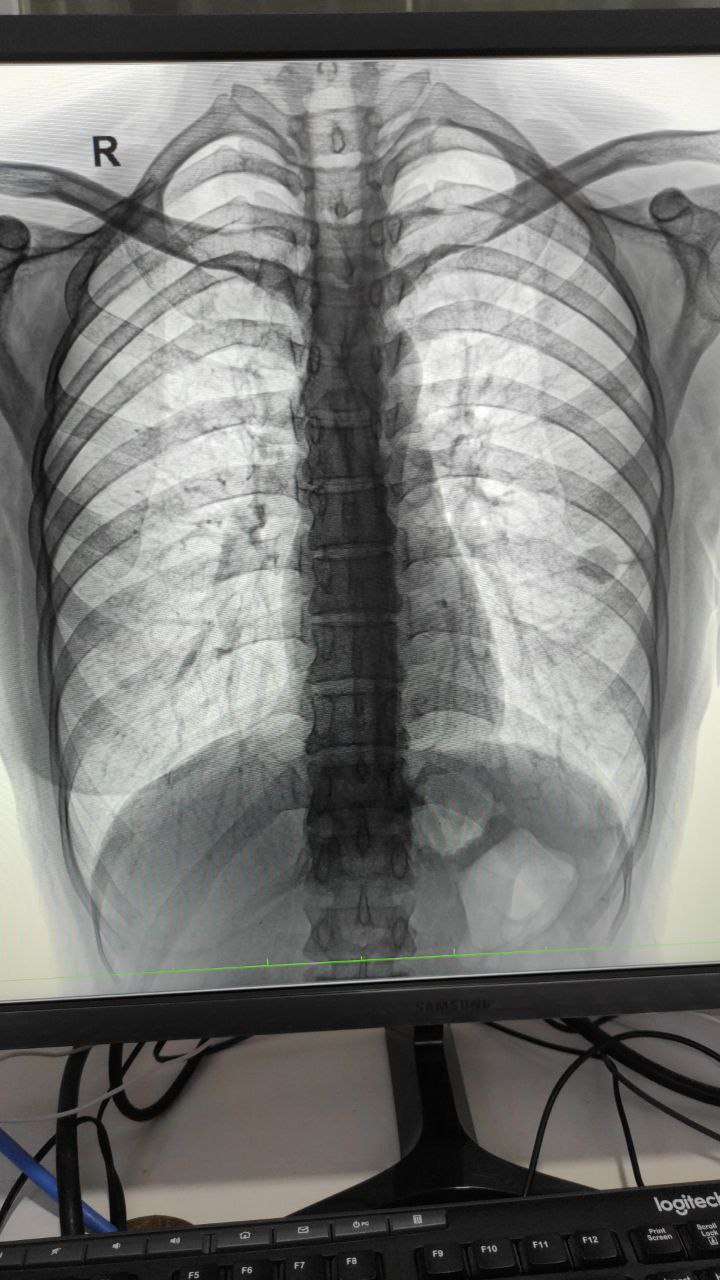

Добрый день. Татьяна. Хотела проконсультироваться по снимку. Обнаружили ковид .вдруг воспаление.. Хотела  уточнить.. Но я так понимаю тут чат для медиков. Уж простите, что внедрилась. Возможно кто-то поможет.